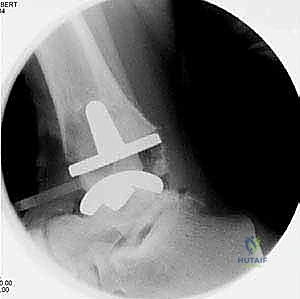

يتم إجراء فحوصات شاملة تشمل الأشعة السينية (X-rays)، والأشعة المقطعية (CT scan) لإنشاء نموذج ثلاثي الأبعاد لكاحل المريض. يساعد هذا د. هطيف في اختيار الحجم الدقيق للمفصل الصناعي وتحديد زوايا القطع بدقة متناهية.

4. تركيب المفصل الصناعي (Implantation)

يتكون مفصل الكاحل الصناعي الحديث عادة من ثلاثة أجزاء:

* قطعة معدنية علوية: تُثبت في عظمة الظنبوب (الساق).

* قطعة معدنية سفلية: تُثبت في عظمة الكاحل.

* قطعة بلاستيكية (بولي إيثيلين عالي الكثافة): توضع بين القطعتين المعدنيتين لتنزلق بسلاسة وتمتص الصدمات، محاكيةً وظيفة الغضروف الطبيعي.

يتم تثبيت هذه الأجزاء بإحكام (إما عن طريق الضغط المباشر لتشجيع نمو العظم حولها، أو باستخدام أسمنت طبي خاص).